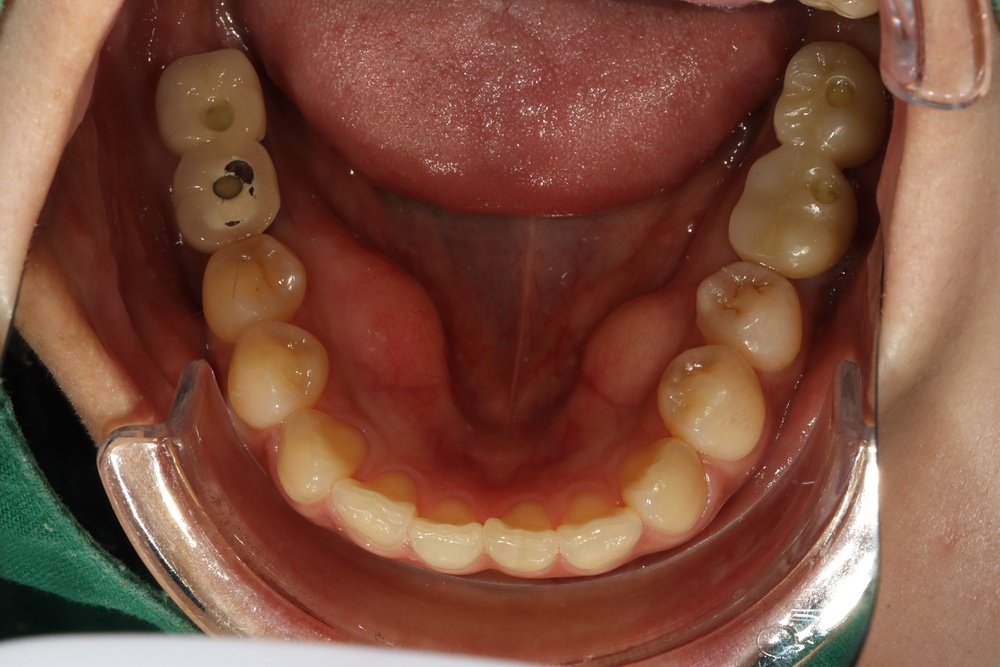

아래쪽 두 번째 어금니(제2대구치)가 선천적으로 없는 결손치로서, 사랑니(제3대구치)가 있으나 앞으로 쓰러져서 잘 안 씹히고 썩어 있습니다.

이런 경우 사랑니를 발치하고 임플란트를 하는 방법도 있으나, 본인 치아를 살리고 싶어하셔서 교정으로 접근하였습니다.

(본원은 교정과 임플란트 모두 다루므로 각 방법의 장단점을 충분히 비교 설명드렸습니다)

부분교정을 통해 누워있던 사랑니를 세웠으나, 씹는 면에 충치가 있습니다.

교정종료 후 보철치료(인레이)를 통해 씹는 기능을 회복시켰습니다.

누워있던 이가 세워져서 음식물이 더 잘 씹히게 되었습니다.

또한 음식물이 끼지 않게 되어 구강위생관리도 원활하게 되었습니다.